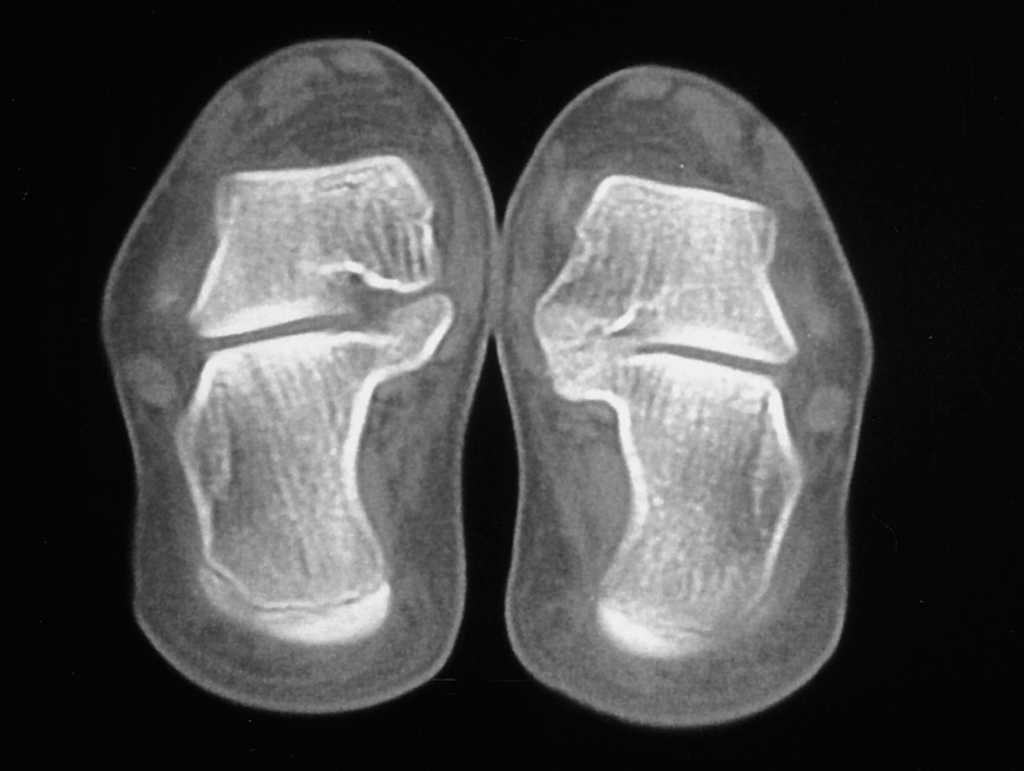

En la mayoría de las sinóstosis C-E se llegó al diagnóstico mediante una radiografía del pie en proyección oblicua (proyección de Sloman) (fig. 1) y pocas veces se precisó de una TAC. Por el contrario, la exploración radiográfica de las sinóstosis A-C sólo permitió, en algunos casos, sospechar una sinóstosis ante la poca definición de la articulación media astrágalo-calcánea, la presencia de un pico dorsal en la cabeza del astrágalo, o la aparición de una imagen en C, pero para concretar el diagnóstico se precisó siempre de una exploración por TAC (fig. 2).

Figura 2. Corte de tomografía axial computarizada (TAC) en el que aparece una sinóstosis astrágalo-calcánea, muy evidente en el lado izquierdo (derecho de la figura).